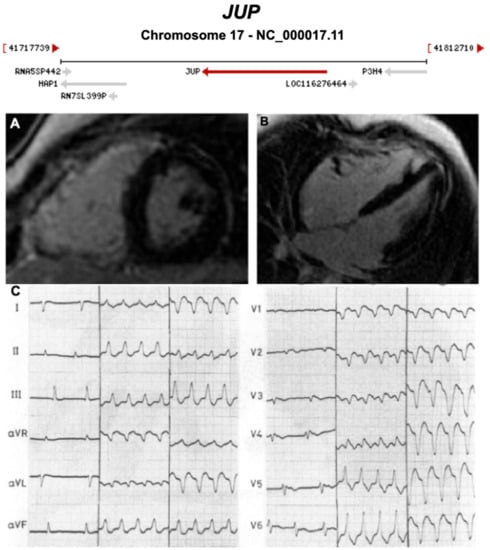

| JUP | Desmosome | 0–1% | AD and AR | RV, BIV | ARVC12 | 17q21.2; 19 | Cardiocutaneous syndrome AR (Naxos) | Definitive for ARVC |

3.1. Desmosomal Genes